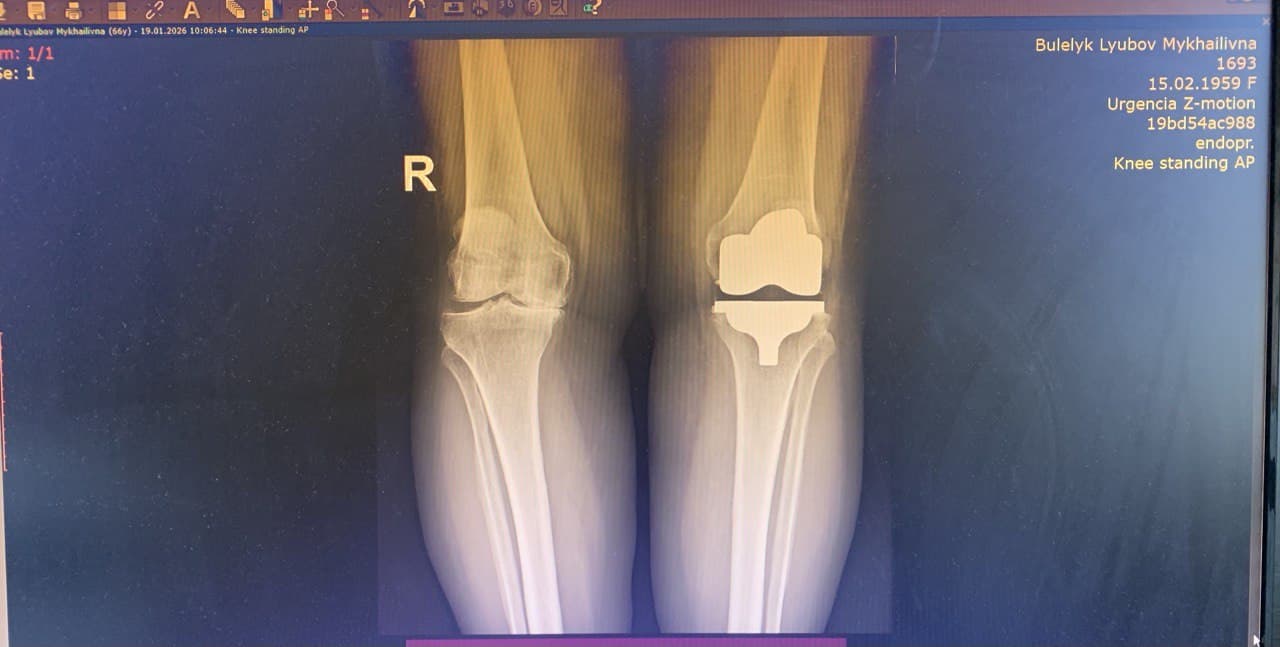

Однією з пацієнток, якій виконали операцію з використанням кінематичного методу, стала Любов Булелик із села Заріччя Делятинської громади. Жінка розповідає, що проблеми з колінами тривали не один рік, однак значно посилилися після перенесеного коронавірусу. У 2023 році після обстежень їй підтвердили виражений артроз і рекомендували операцію. Спершу вона намагалася лікуватися консервативно.